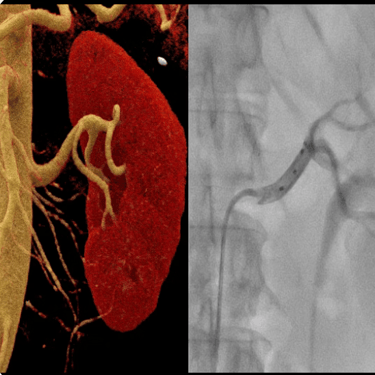

Renal denervation is a minimally invasive procedure designed to treat resistant hypertension, a condition where blood pressure remains high despite at least three medications. It targets the overactive sympathetic nerves surrounding the renal arteries, which contribute to elevated blood pressure.The procedure is performed using a catheter inserted via the femoral or radial artery, which delivers radiofrequency energy or ultrasound waves to disrupt these nerves. This reduces their excessive signalling, leading to a sustained blood pressure reduction. Renal denervation is particularly beneficial for patients with difficult-to-control hypertension, helping lower the risk of heart attack, stroke, kidney disease, and other complications.

Find more Information at oxfordrenaldenervation.com